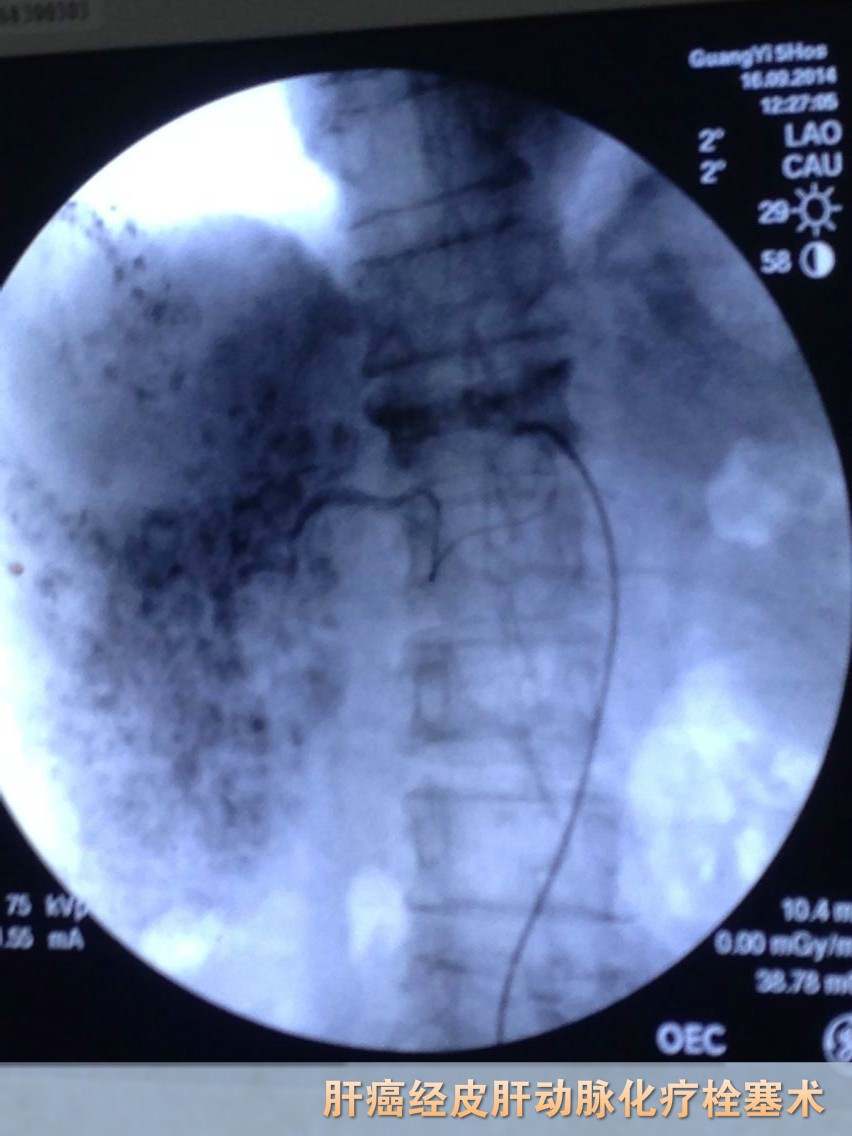

随着医疗技术的不断提高,介入技术在恶性肿瘤的治疗上发挥着越来越重要的作用。该技术是在大型X线电视透视造影机引导下将导管精确地选择性插入肿瘤病灶相关的供血靶动脉内,将高浓度的化疗药物精确地直接灌注病灶,杀伤力强、疗效高;而瘤灶周围及全身无关组织器官药物分布少,全身副反应小。灌注后,再用栓塞剂堵死瘤血管床,切断肿瘤的营养供应,“饿死”瘤细胞;化疗药物的精确打击与切断肿瘤营养线双管齐下,有效地杀伤了肿瘤病灶,适用于治疗绝大多数中晚期患者、各种部位的恶性肿瘤。该项技术无需开刀暴露病灶,因此能减少病人痛苦,最大限度保护肿瘤周围正常组织器官功能的完整性。

目前,我院肿瘤专科采用肿瘤微创介入治疗,如介入栓塞、微波、射频等技术,并联合肿瘤免疫细胞治疗等多种途径综合治疗模式,成功地对多种中晚期肿瘤患者如原发性肝癌、肺癌以及胃肠道等肿瘤进行治疗。

1、肝动脉化疗栓塞联合射频、微波消融治疗各期肝癌